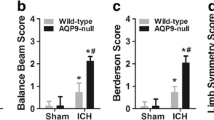

Next, we wanted to determine if the pre-treatment with VEGF-C would affect locomotor activity, sensorimotor functions, or neurological outcome post-stroke. First, the locomotor activity of the mice was studied using the latency to move test at 3 dpi in mice treated with the AAVs 14 days before tMCAo (Fig. 3a). As expected, the tMCAo;Ctrl mice showed significantly increased latencies than the sham;Ctrl mice (p < 0.05, Fig. 3c). In contrast, tMCAo;VEGF-C mice did not show significantly increased latencies when compared with the sham;VEGF-C group (Fig. 3c). This suggested a mild VEGF-C-induced improvement in locomotor activity during the early phase after stroke at the time of testing.

VEGF-C treatment improves gait and decreases neurological deterioration post-stroke. a, b Experimental outlines showing time points for AAV-administration, ischemic surgery, behavioral testing, and sample taking. c Latency to move test-results from day three post-surgery of mice the Ctrl or VEGF-C group. d Comparison of several temporal, spatial, and interlimb coordination parameters obtained from CatWalk gait analyses between ischemic mice at seven dpi of either Ctrl or VEGF-C treatment. e–g Neuro score comparison at (e) 3 or (f) 7 dpi of ischemic mice treated 35 days before surgery with Ctrl or as VEGF-C, as well as of mice treated (g) at 14 days prior to surgery. h Comparison of sensorimotor skills using the corner test in sham and ischemic mice treated with Ctrl or VEGF-C at 35 days prior to infarction. n = 6–19; data points shown in graphs c–h represent individual mice; statistical analyses were carried out using either two-tailed Student’s t test, or two-way ANOVA with Tukey’s post hoc test for multiple comparison, *p < 0.05, **p < 0.01, ***p < 0.005

A more detailed quantitative assessment in locomotor disturbances caused by ischemic stroke was done by applying CatWalk gait analyses [25, 29] at 7 dpi in mice injected with the AAVs 14 days before surgery. VEGF-C-treated mice showed significant improvement of locomotor disturbances post-stroke in comparison with the Ctrl-treated mice. VEGF-C-induced improvements included temporal, spatial, and interlimb coordination parameters (Fig. 3d). As temporal parameters, the terminal dual stance on the right front (RF) (p < 0.005) and hind (RH) paws (p < 0.004), and the initial dual stance of left front (LF) (p = 0.01) and hind (LH) paws (p < 0.01) were significantly reduced in the VEGF-C-treated mice (Fig. 3d). VEGF-C treatment resulted in improved spatial values of the minimal intensity of the RF paws (p = 0.02), as well as of the mean intensity of the LH paws in comparison with Ctrl treatment (p < 0.05; Fig. 3d). Furthermore, VEGF-C improved the interlimb coordination as shown by support three, a parameter that describes the number of paws used to support body weight during a step cycle [25] (p = 0.0016) and coupling (LF to RH, a temporal relationship between the placements of the LF and the RH paw within one step cycle; p < 0.001). These findings thus demonstrate that VEGF-C treatment improved locomotor gait abilities post-stroke.

VEGF-C Treatment Improves General and Focal Neurological Outcomes Post-Stroke

In addition to gait impairment after ischemic stroke, we also accessed general and focal neurological deficits, which are eminent after focal ischemia, by neurological scoring according to Orsini and colleagues [31]. Mice injected with VEGF-C 35 days before tMCAo surgery (tMCAo;VEGF-C; Fig. 3b) showed significant improvement in neurological outcome both at 3 and 7 dpi when compared with the tMCAo;Ctrl group (p < 0.05, Fig. 3e, f). Mice treated with VEGF-C 14 days prior tMCAo surgery (Fig. 3a) also showed a trend toward a better neurological outcome when compared with tMCAo;Ctrl (p = 0.0531, Fig. 3g).

Corner test, measuring sensorimotor functions, showed a significant disturbance after ischemia (p < 0.001). However, in this test, we did not find a significant difference between the groups treated with VEGF-C or Ctrl 14 days before surgery (Fig. 3h). Collectively, these results demonstrate that i.c.v delivery of VEGF-C before stroke significantly improves early locomotor activity, locomotor gait disturbances, as well as general and focal neurological outcome post-stroke, whereas it has no effect on tested sensorimotor functions.